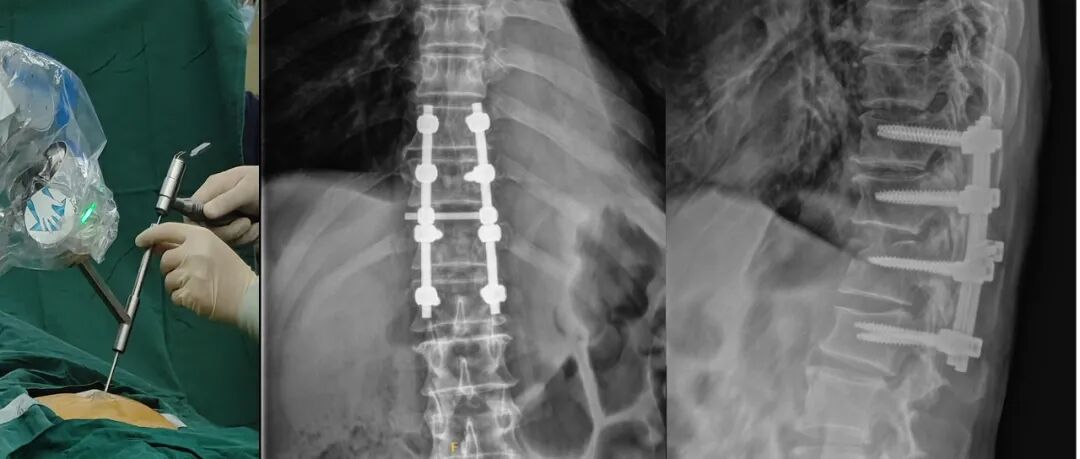

脊柱手术的精准度,往往受限于操作中的“隐性干扰”——置钉时易受肌肉牵拉偏移,从而影响手术效果,也导致很多手术方法始终难以在临床应用。联影智融脊柱创伤一体化骨科手术机器人采用六轴联动高刚性医用机械臂,定位精度达到亚毫米级,配合患者实时跟踪系统动态补偿体位误差,兼顾操作便利性的同时显著提升手术精度,可实现经皮钉道制备开放置钉术、经皮穿刺皮下经肌间微创置钉术等创新术式。

术中照片及术后X线片

其中,机器人辅助颈椎前路椎弓根置钉(ATPS)技术是本次分享的重点突破。ATPS固定技术是治疗多节段颈椎疾病和严重颈椎损伤的有效方法,在明显改善神经功能的同时获得较好的融合效果。该技术通过一次手术从前路减压植骨融合后置入椎弓根螺钉,能有效解除椎管前方的压迫,并且具有椎弓根坚强固定的优点,对于那些需要在前路行多节段椎体次/全切除后稳定性重建的患者具有重要的意义。作为首个系统性评估该技术的研究,其可行性、重复性及安全潜力已得到验证,并成功实现临床转化,填补相关临床应用空白。